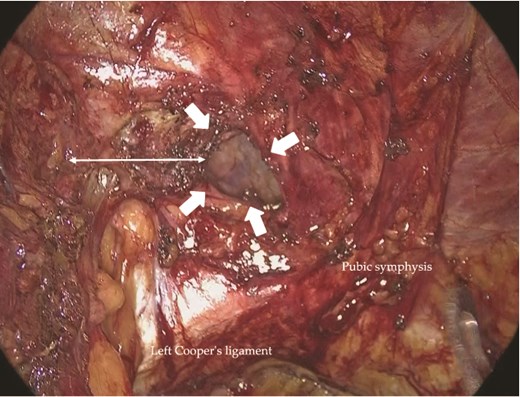

Intraoperative view of the left inguinal region. The recurrent hernia orifice (arrows) and pseudosac were located adjacent to the pubic symphysis. Dense fibrotic adhesions were present around the pseudosac.

On the left, the recurrent hernia orifice was identified adjacent to one of the mesh plugs, with the pseudosac firmly adherent to the plug (Fig. 5). After careful sharp and blunt dissection, a recurrent orifice was clearly exposed in the left pubic region and classified as R1M2 (Fig. 6). A circumferential margin of ~2.5 cm was secured around the defect. The laterally placed plug did not interfere with the repair and was left in situ. A 15 × 10 cm self-gripping mesh (ProGrip™) was placed to cover the recurrent defect with a 2.5 cm margin and was supplemented with tacker fixation because overlap was limited (Fig. 7). Although the left-sided mesh covered the right hernia orifice, overlap on the right was insufficient (Fig. 8), so an additional mesh was applied for reinforcement. The right-sided high peritoneal incision was sutured and closed in a standard fashion (Fig. 9). The postoperative course was uneventful. At 5-month follow-up, there was no clinical evidence of recurrence.